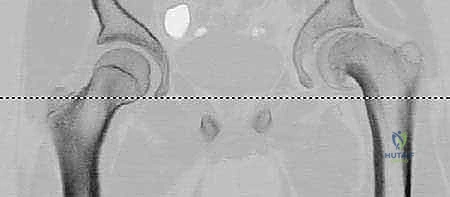

* علامة دريمان (Drehmann Sign): وهي العلامة التشخيصية الأهم. عند محاولة الطبيب ثني ورك المريض (Flexion)، يتجه فخذ المريض تلقائياً نحو الخارج (External Rotation) ولا يمكن ثنيه بشكل مستقيم.

- تُطلب بوضعيات محددة: أمامي خلفي (AP) ووضعية الضفدع (Frog-leg lateral).

- علامة كلاين (Klein's Line): في الأشعة الأمامية، يجب أن يتقاطع الخط المرسوم على الحافة العلوية لعنق الفخذ مع جزء من رأس الفخذ. في حالة الانزلاق، لا يتقاطع هذا الخط مع الرأس، مما يؤكد التشخيص.

- يستخدمه الأستاذ الدكتور محمد هطيف لتقييم درجة التشوه الميكانيكي بدقة متناهية، وقياس زاوية الانزلاق الخلفي (Slip Angle)، وتحديد مقدار العظم الذي يجب قطعه وتدويره خلال الجراحة لضمان تصحيح مثالي 100%.